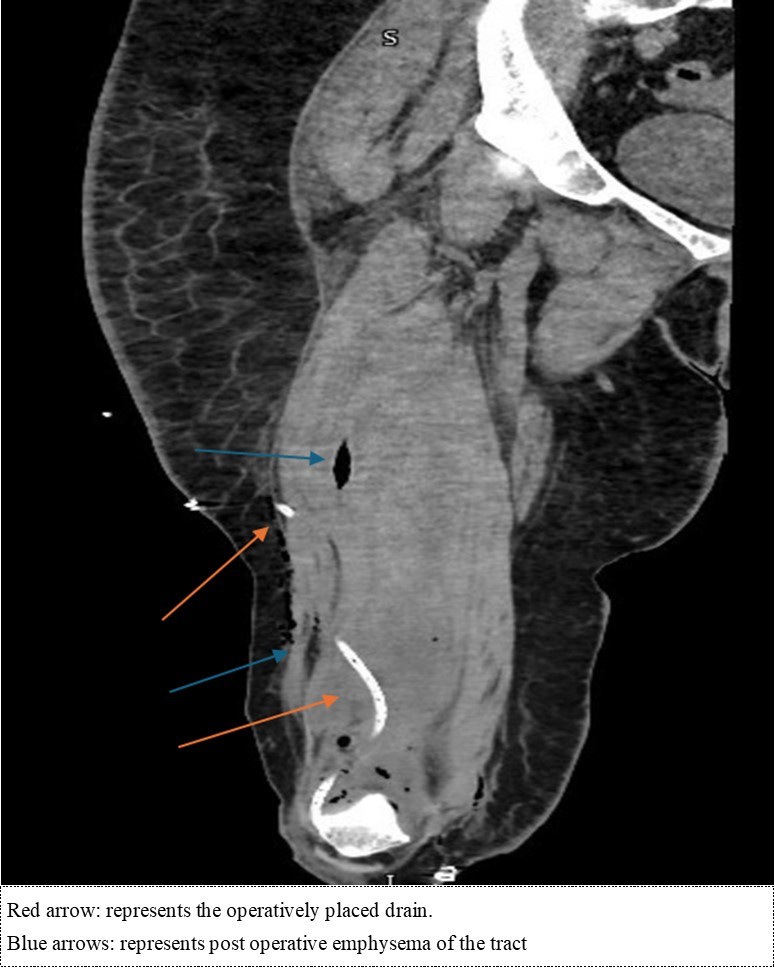

52-year-old female known to have traumatic brain injury (TBI) since the 1980’s with associated tremors and no other medical comorbidities had been complaining of right sided knee pain for multiple years. She notes that due to the tremors from her TBI, she had been deviating a lot of weight over her right side. However, for 6 months, the patient had been complaining of worse than usual right knee pain, for which she had been referred to the sports medicine clinic by her primary care physician. In the clinic, intra-articular joint injection (IJI) without ultrasound guidance was discussed and performed. 6 days following the joint injection, she had noted significant worsening of her knee pain with associated swelling and systemic symptoms including fevers and night sweats. She had presented to the emergency department. Lab work revealed a C-reactive peptide levels of 467.3 mg/L, a white blood cell count of 15.2x103 u/L and erythrocyte sedimentation rate of mm/hr. Arthrocentesis was performed with purulent material extracted, negative crystals, and notable for 175,0000 nucleated cells with 98% polymorphonucleated cells. She was started on linezolid 600 mg twice daily and taken for an operative knee washout. During the operation, a tract was noted to extend from the joint capsule to the lateral aspect of the thigh. External pressure to the lateral thigh was used to express purulent material through the tract, then an incision and drainage was performed to ensure complete extraction of the purulent matter with drain placement. CT scan of the right femur and knee without contrast was then performed following the operation (Figure 1a. and Figure 1b).

Figure 1a.Sagittal cut of the non-contrasted CT of the femur – soft tissue

Figure 1b.Coronal cut of the non-contrasted CT femur – soft tissue